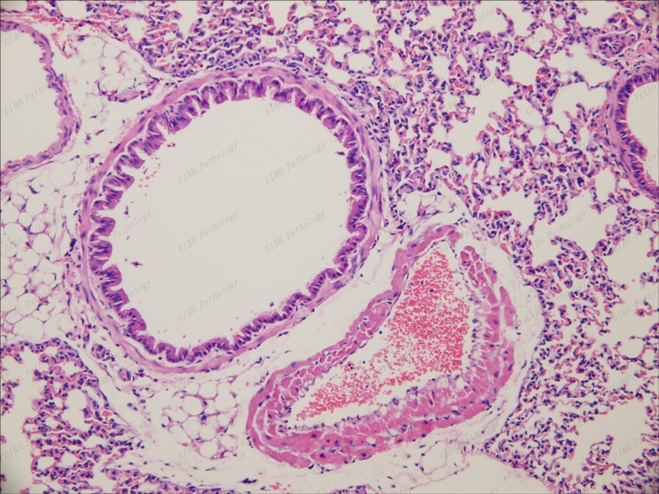

肺20